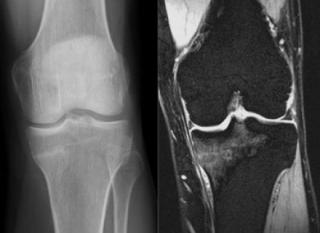

(Левый) При МРТ в сагиттальной плоскости на Т1ВИ определяется нарушение целостности верхнемедиального пучка подошвенной пяточно-ладьевидной связки. Оценивать связку следует во всех трех плоскостях, чтобы исключить эффект частичного объема.

(Правый) У этого же пациента при МРТ в сагиттальной плоскости в режиме STIR подтверждается разрыв верхнемедиального пучка подошвенной пяточно-ладьевидной связки она растянута и утолщена. Отек костного мозга в головке таранной кости обусловлен отсутствием ее поддержки подошвенной пяточно-ладьевидной связкой и нарушением биомеханики движения. (Левый) У этого же пациента при МРТ в коронарной плоскости на ППВИ определяется гетерогенная структура утолщенного подошвенного пучка подошвенной пяточно-ладьевидной связки. Вблизи выявляется нечеткий контур разорванной большеберцово-пяточно-ладьевидной связки Сухожилие задней большеберцовой мышцы окружено аморфным мягкотканным субстратом.

(Правый) У этого же пациента при МРТ в коронарной плоскости на Т2ВИ в режиме FS визуализируется дефекта между волокнами подошвенной пяточно-ладьевидной и больше-берцово-пяточно-ладьевидной связок. Также выявляется выраженный тендовагинит задней большеберцовой мышцы. (Левый) При МРТ в аксиальной плоскости на ППВИ в режиме FS определяется интактный продольный нижний подошвенный пучок подошвенной пяточно-ладьевидной связки. Медиально выявляется скопление жидкости, обусловленное разрывом верхнемедиального пучкам.

(Правый) У этого же пациента при МРТ в аксиальной плоскости на ППВИ в режиме FS на срезе, проходящем чуть выше, визуализируется разрыв большеберцово-ладьевидного и большеберцово-пяточно-ладьевидного пучков поверхностного слоя дельтовидной связки. Также выявляется тендинопатия задней большеберцовой мышцы.